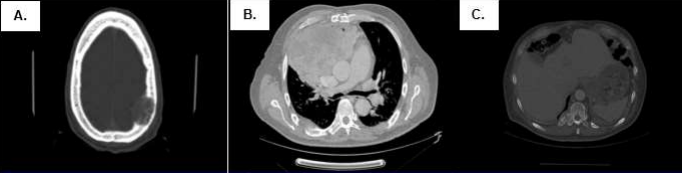

In May 2016, the patient was hospitalized in the Medical Oncology Service. He presented stable vital functions and underwent laboratory and imaging evaluations. He underwent a multislice spiral tomography of brain, thorax, abdomen and pelvis, evidencing a heterogeneous mass of 150mm x 100mm x 151mm in anterior mediastinum, infiltrating pleura and adjacent cortical bone, associated with nodes in internal mammary chain of 10mm, mediastinal adenopathies of 12mm, right pleural effusion and lytic lesions in cranial calotte, D10 – D12 and L3 – L5 (Figure 2). Also, a trucut biopsy of the mediastinal mass gave an anatomopathological diagnosis as papillary adenocarcinoma of thymus, and immunohistochemical tests were positive for Ki-67 (15%), CD5, CD117, and negative for p53, CK20, TTF-1 (Figure 3A).

Figure 2. Tomography at diagnosis of the disease (05/30/16). There is evidence of (A) lytic image in cranial calotte, (B) anterior mdediastinal mass of 150mm x 100mm x 151mm infiltrating adjacent structures, and (C) lytic lesions in costals arches y vertebrals bodies.